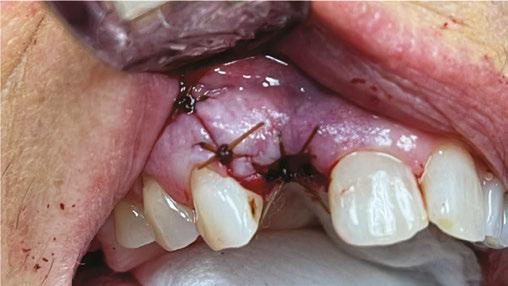

Almost falling asleep at the wheel, I barely managed to drive home. Once home, I made my way to bed and fell right to sleep. At 1 a.m., I awoke bathed in sweat, simultaneously yet uncontrollably shivering and feeling downright awful. I knew something was dangerously wrong. I woke up my wife, and we headed to the hospital ER, where they immediately took my vitals. My blood pressure was extremely low, my heart rate was racing out of control, and my temperature was burning up at 103.3 F. The diagnosis was sepsis! After a CT scan of the abdomen and blood work, I was placed on IV antibiotics. I won’t go into the horrible details of 8 miserable days in the hospital and 4 weeks of IV antibiotics, which were delivered through a picc line (Figure 1) inserted into my arm. I thank G-d every day that I’m alive and able to go back to caring for my family, friends, staff, colleagues,

and patients and cherishing every moment I’m still in this beautiful world. It makes me wonder if I, as a healthcare professional, couldn’t make a timely diagnosis of my own sepsis setting in, how could the average person? Sepsis is a major life-threatening event that dentists must be aware of. Be prepared to advise your patients when sepsis is suspected to head to the hospital ER, because that timely response just might save their lives.

Figure 1: PICC line removed after 4 weeks, which went from the inner arm through the brachial vein towards the